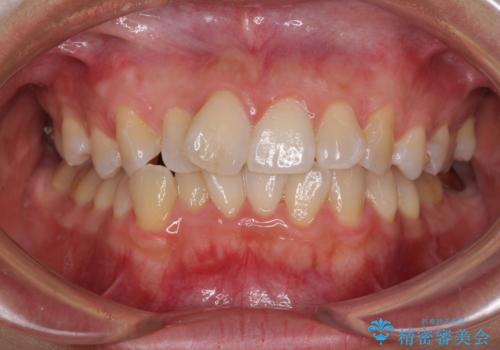

前歯のデコボコをインビザラインでスッキリと仕上げる

- 上下前歯のデコボコと奥歯の銀歯を気にして来院された患者様です。

口元をインビザラインにより歯列を整え、その後に失活している奥歯をオールセラミッククラウンにて補綴治療することとしました。

長時間のマウスピース装着に協力いただき、自然な口元に仕上げることができました。

気になっていた銀歯もオールセラミッククラウンで本物の歯のようになり、患者様には大変満足していただきました。